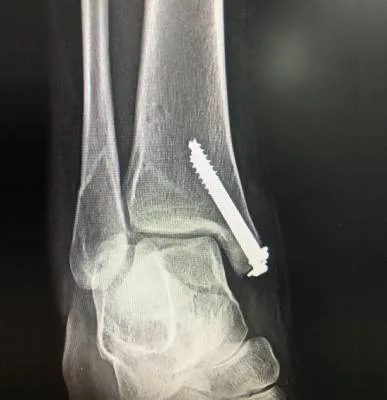

Dr. Haytham Elkhatib is a distinguished orthopaedic surgeon specializing in comprehensive musculoskeletal care. With expertise in trauma, fracture treatment, and advanced interventional joint injections, he offers innovative solutions for various conditions.

I had surgery with Dr. Haytham, and I’m very happy with the results. He previously operated on my leg after a fracture, and that surgery was very successful. Recently, I had another surgery on my knee, which was done in the simplest and most professional way. After the operation, I was able to return to my normal life — I can play football and be active again after a long time of not being able to. Dr. Haytham and his team took great care of me throughout the process, and I truly thank him for his excellent work and dedication